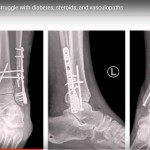

The struggle with diabetes, steroids, and vasculopathy in Ankle Fractures

Courtesy: Saqib Rehman MD Director of Orthopaedic Trauma Temple Unviersity Philadelphia USA